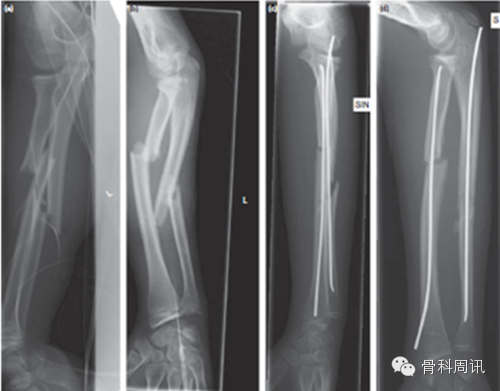

患兒的年齡會影響治療策略,學齡前兒童通常不采用任何接骨術治療。學齡兒童最常見的手術是彈性髓內釘(ESIN)固定,這是該年齡組患兒前臂骨幹骨折主要的固定方法。與年齡較小的兒童相比,ESIN的並發症更常見於10歲以上的患兒。現在至少有80%的前臂骨折需要由ESIN手術固定。細的髓內釘釘本身提供的穩定性不盡人意。然而,髓內釘產生令人滿意的穩定性來自於其彎曲後產生的張力;彎曲的髓內釘在兩個骨頭間共同建立圍繞整個前臂骨折的張力架(圖3)。ESIN通常是由鈦或不鏽鋼製成。BESIN(生物可降解-彈性穩定-髓內-釘)是一個創新技術,正在進行臨床評估。

圖3 學齡兒童的不穩定前臂骨幹骨折已接受手術治療並由ESIN固定(a,b)。細髓內釘的直徑隻覆蓋髓內骨道最小直徑的40%(c,d),但由於髓內釘彎曲,接骨術的穩定性仍然令人滿意。ESIN即彈性穩定髓內釘。